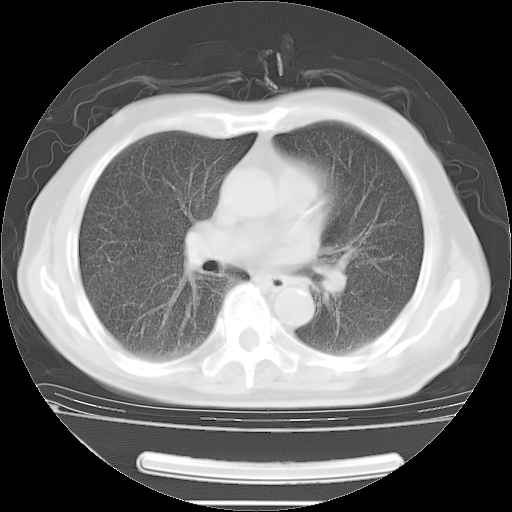

今天复查肺部CT,发现双肺广泛磨玻璃样改变。所以我把3月19日和5月9日相隔50天的肺部CT上传。请大家会诊。

5月9日肺部CT(在4月27日齐鲁医院肺部CT描述部分肺组织磨玻璃样改变,12天后肺组织广泛磨玻璃样改变)

2009年5月9日肺部CT

大致读了系列胸部CT:纵隔窗无明显异常,肺窗:从4、27至今:主要是双肺中下野外带可见毛玻璃样改变,目前处于急性肺泡炎阶段,至于原因考虑1、结替组织或胶原血管性疾病所致?2、恶性疾病如恶组在肺部所致的表现或细支气管肺泡癌?3、药物或其它原因如肺蛋白沉着症所致肺泡炎目前不太可能?总之,明天就去请我院的呼吸科、感染科、血液科和临免专家会诊哈。